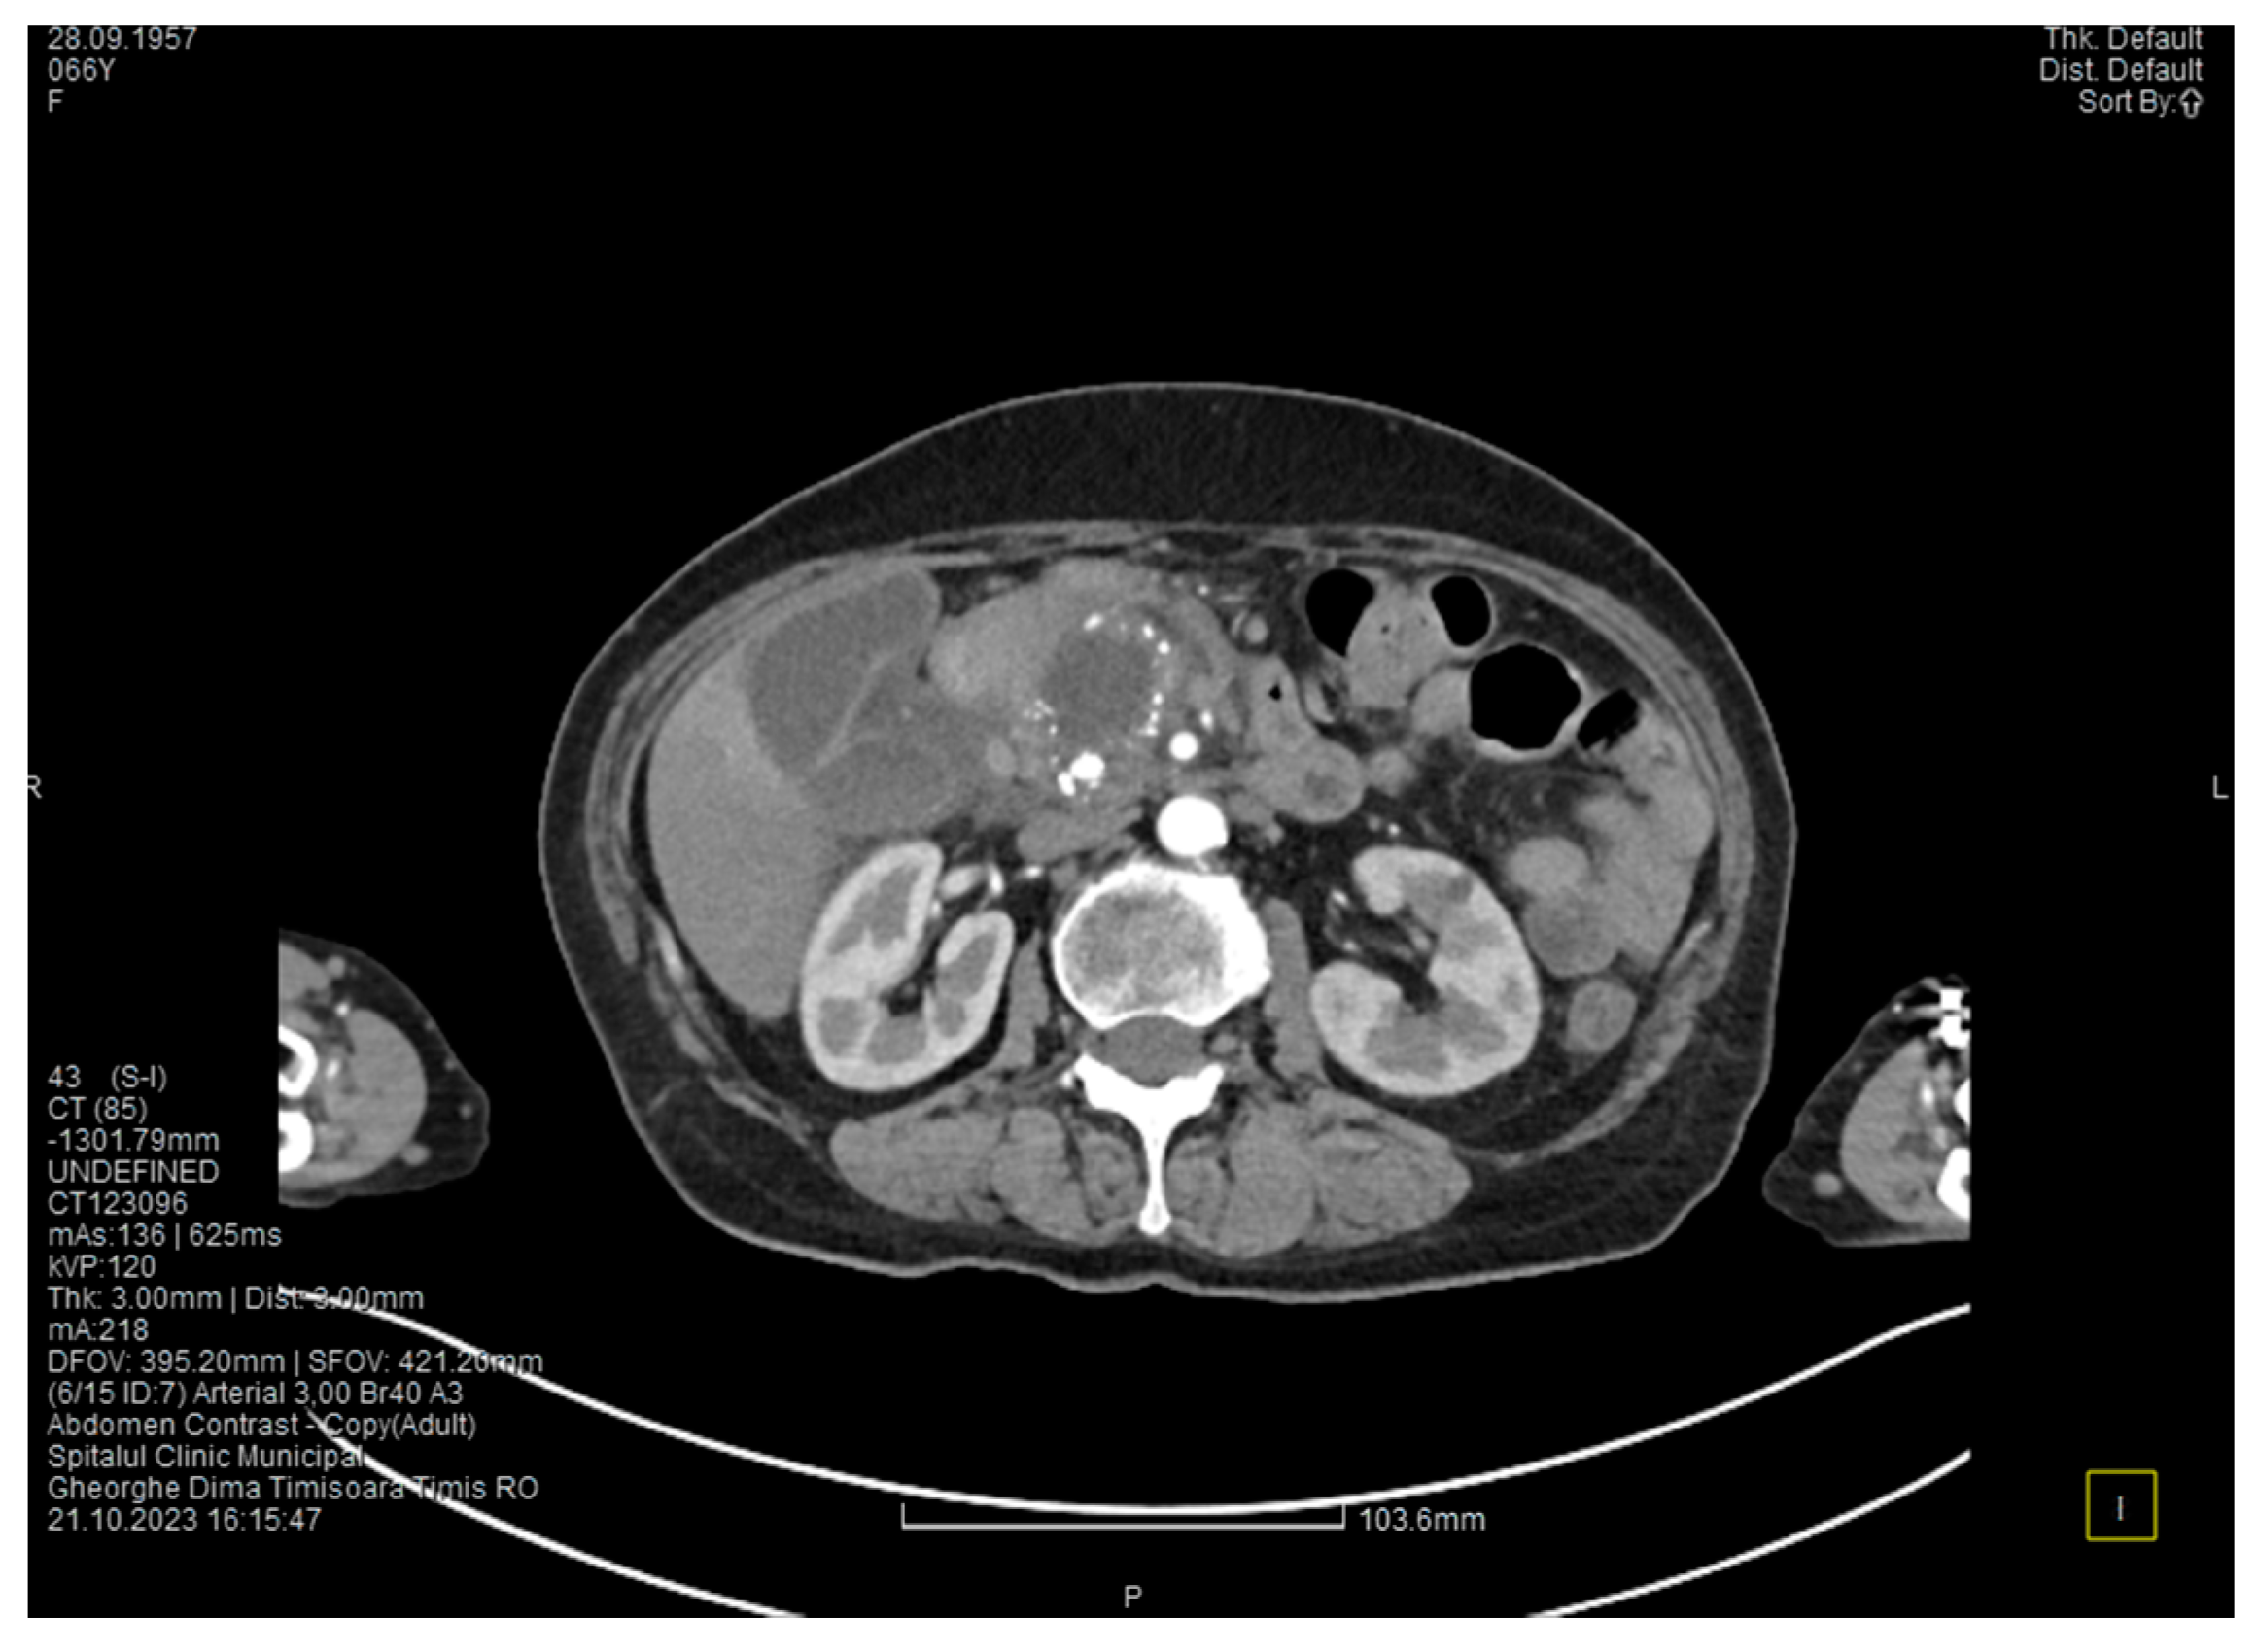

The contrast-enhanced computed tomography showed changes suggestive of chronic pancreatitis, with multiple very small calcifications of the pancreatic tissue, dilatation of the Wirsung duct in the corporeo-caudal area measuring approximately 15 mm (Figure 3), and a narrowing of the Wirsung tract in the cephalic area where calcareous conglomerates were present. In the anterior cephalo-uncinate area, an oval cyst measuring 31/28 mm was detected (larger than it was one month ago) (Figure 4). In the peri-cephalo-uncinate area, we observed densifications of the adjacent fat extending towards the gastric antrum, the root of the mesentery, and the hepatic flexure of the colon. There was a mild inflammatory enlargement of the peripancreatic lymph nodes and the ones situated in the hepatic hilum. We also noticed a slight dilatation of the intrahepatic bile ducts and the common hepatic duct, and diffuse atheromatosis of the aorta, the iliac, and the common hepatic arteries. We performed a gastroscopy, which revealed a normal esophagus, stomach, and duodenal bulb; however, it was impossible to advance the endoscope towards the D2 part of the duodenum due to the significant edema of the duodenal mucosa and the partial stenosis of the duodenal lumen.

Figure 3. The second CT evaluation shows a dilated Wirsung duct and calcifications in the pancreatic tissue.

Figure 4. The second CT scan shows a cyst in the pancreatic head and calcifications in the pancreatic head and groove area.